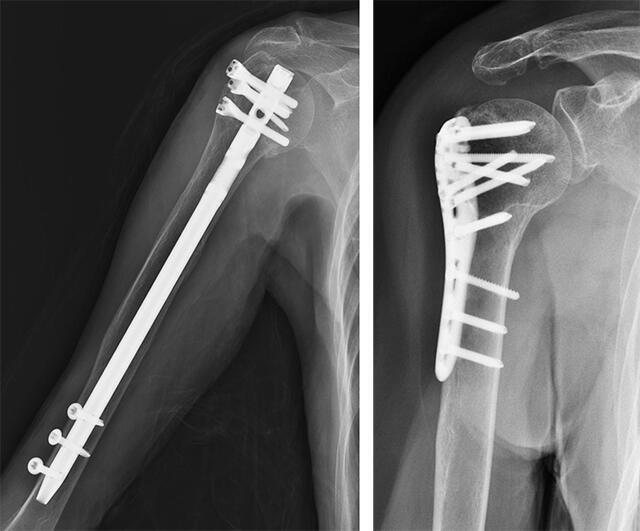

多くの場合、上腕骨近位端および上腕骨幹部中位の骨折では、骨折した端部が互いに近くに留まることが多いため、手術は必要ありません。これにより、上腕骨が自然に治りやすくなります。ただし、必要に応じて、腕が動かないようにし、肩を安定させるために、スリング、装具、または添え木を着用する必要があります。場合によっては、プレート、ネジ、ロッドを使用した手術が必要になる場合や、場合によってはプロテーゼを使用して肩関節を置換する必要がある場合もあります。

遠位骨折およびより重度の近位または中間骨幹部骨折には、通常、手術が必要です。外科医が使用できる主なアプローチは 2 つあります。

- ピンとネジ。骨片が皮膚に突き刺さる開放骨折の場合、骨折端をきれいにするために手術が必要になり、上腕骨の骨折端を所定の位置に保持するためにピン、ネジ、プレートが使用される場合があります。